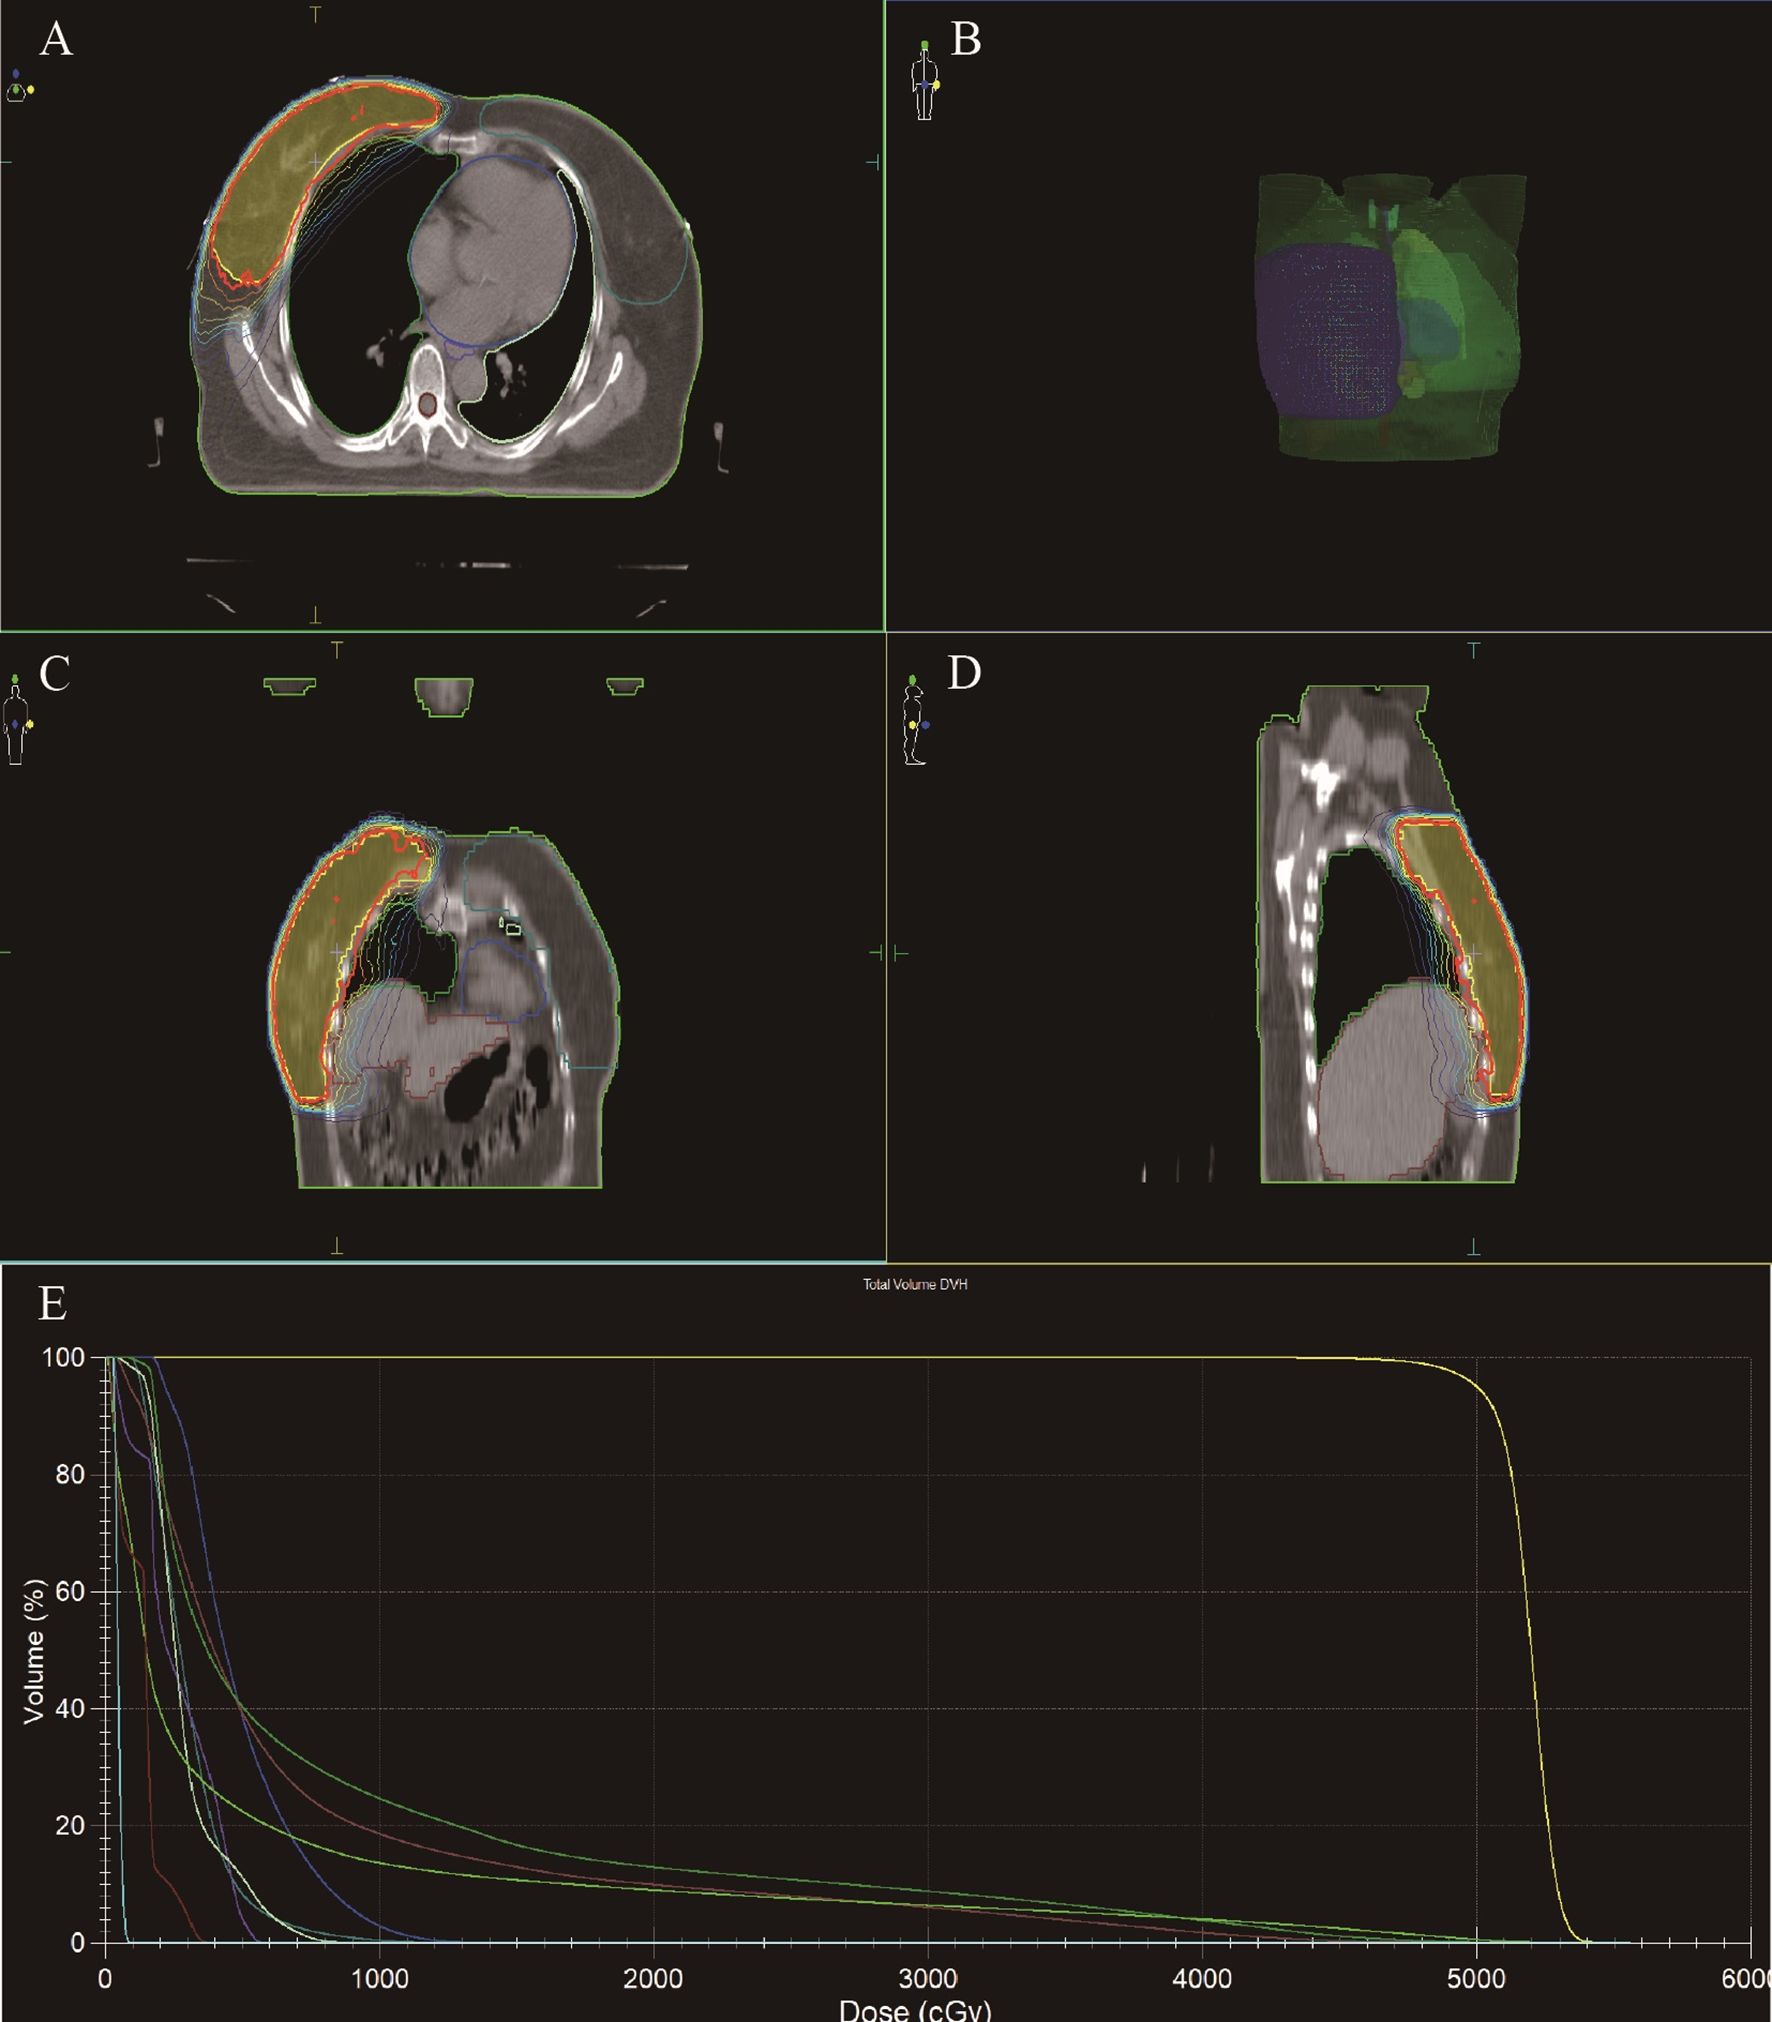

The patient underwent a secondary procedure to ensure negative margins. Preoperative ultrasound of the right breast showed slightly enhanced localized echogenicity at 7–9 o’clock, with a size of 3.5×3.2×2.4 cm, unclear borders, irregular morphology, no obvious blood flow signal on color Doppler flow imaging, and no obvious enlargement of lymph nodes in both axillae (Figures 1A, B). Contrast-enhanced magnetic resonance imaging (MRI) scan of the breast showed multiple scattered small nodular foci of significant enhancement in the right breast, with most of the lesions having a diameter of 2–3 mm and clear and smooth borders. One of the lesions was larger (diameter about 6mm) and located in the outer and lower quadrant, having a smooth border, with time-signal intensity curve (TIC) of the plateau pattern and significant enhancement of the ductal region seen beside it. The upper edge of the skin of the right breast was not smooth, and the reconstruction image showed a rounded area of slightly high signal intensity (Figure 1C). The right breast mass was then excised, and the upper, lower, inner, and outer margins of the excised tissue were collected and sent for examination. During the operation, and a bulky piece of breast tissue was seen, with size 7.5 × 6 × 1.7cm, and a grayish-yellow area was seen at the marking place, 0.8 × 0.6 × 0.5cm, with medium texture. The remaining breast tissue appeared grayish white, interspersed with areas of grayish yellow and was soft in texture. No cancerous tissue was seen at the margins of the excised breast tissue (upper, lower, inner, or outer). The tumor cells were arranged in a multinodular, solid, papillary arrangement, while the tumor cells themselves were hypercolumnar cytoplasmic, eosinophilic, and rich in mitochondria. Dispersed in the nodules were single round to oval mesonuclear grade cells. The oval nucleus showed invaginations of the nuclear membrane parallel to the long axis of the nucleus or a nuclear furrow with folded nuclear membrane, and the nuclear furrow invagination was encapsulated into the cytoplasm as intranuclear pseudo-inclusion bodies (Figures 2A1-3). The results of immunohistochemistry were as follows: ER (-), PR (-), HER-2 (-), Ki-67 (+ about 10%), AR (-), CK5/6 (+), CK7 (+), P63 (-), Calponin (-), SIA (-), SMMHC (-), GCDFP-15 (-), GATA-3 (-), TTF1 (-), CD68 (histiocyte+), CD163 (histiocyte+) (Figures 2B–E). On the basis of the investigative results, the patient was treated with local radiotherapy of the right breast after surgery, with planning target volume of 50Gy/25Fx (Figures 3A–D, Table 1). Dose Volume Histogram (DVH) shows, for any given point on a curve, the corresponding dose (X-value) and volume (Y-value) can be determined. For example, the CTV (Clinical Target Volume) curve shows that 100% of the volume received at least 36 Gy, and 95% of the volume (as per our planning goal) received the prescribed dose of 50 Gy. Steep curves (e.g., CTV) are ideal for target volumes, indicating a homogeneous dose with a sharp fall-off outside the target. Gradual curves (e.g., Lung-R) are typical for OARs(Off-Axis Ratio), showing that a gradient of doses is delivered across the organ. No acute adverse events of grade 2 or higher (according to CTCAE v5.0 criteria) during the radiotherapy was found. The patient was scheduled for periodic follow-up. This comprehensive surveillance strategy encompassed serial tumor marker evaluation (CEA, CA 125, CA 15-3), breast and abdominal ultrasonography, with the former including detailed inspection of the axillary, supraclavicular, and infraclavicular lymph nodes. Cross-sectional imaging via CT was utilized for the chest and head, supplemented by whole-body bone scintigraphy to screen for osseous metastases. Every 3 months for the first year, every 6 months for the second year and then annually thereafter. At the most recent follow-up visit in Aug, 2025 (approximately 24 months post-treatment), the patient remained asymptomatic with no clinical or radiological evidence of local recurrence or distant metastasis. The detailed timeline of key events related to the disease has been showed in Table 2. The resected cancer tissue was subjected to next-generation sequencing (NGS) using a GENESEEQPRIME® pan-cancer panel covering approximately 1.5 Mb of the coding regions of over 400 genes (including exons, fusion-associated introns, variable shear regions, and specific microsatellite (MS) locus regions of more than 400 genes related to tumor targeting, diagnosis, prognosis, and tumor development). The TMB was calculated as 2.1 mutations/Mb, which is classified as TMB-Low based on the established cut-off of ≥ft mut/Mb for panels of this size. The results of NGS revealed that our patient had a missense mutation in exon 20 of the p.H1047R (PIK3CA), with a mutation abundance of 25.00%, and p.R172T exon 4 missense mutation in IDH2, with a mutation abundance of 21.91%. Additionally, 2.1 mutations/Mb, indicating a low tumor mutational burden (TMB), sorted in the top 84.59% were noted (Figures 4A–C). The mutational sites of enzymes related to polymorphisms in drug metabolism are as follows: ERCC2 gene polymorphic mutation, XRCC1 Q399R pure-sum mutation, UGT1A1 polymorphic mutation, TYMS-6bp/-6bo polymorphic mutation, CYP2B6 gene pure-sum polymorphic mutation, and NQO1 gene polymorphic mutationality (Table 3). Mineralocorticoid receptor (MR)-related genes and MS-high (MSI-H) were not detected, and HLA-I typing was determined to be partially pure-sum (Table 4).

Figure 1. Preoperative imaging results of TCCRP. (A, B) Ultrasound imaging before the patient underwent a secondary procedure. (C) MR enhancement scan before the patient underwent a secondary procedure. Axial view of a T1-weighted contrast-enhanced fat-suppressed MR image obtained before the patient underwent a secondary procedure.